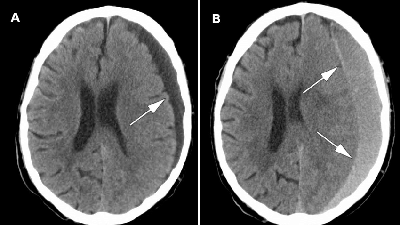

خونریزی مغزی